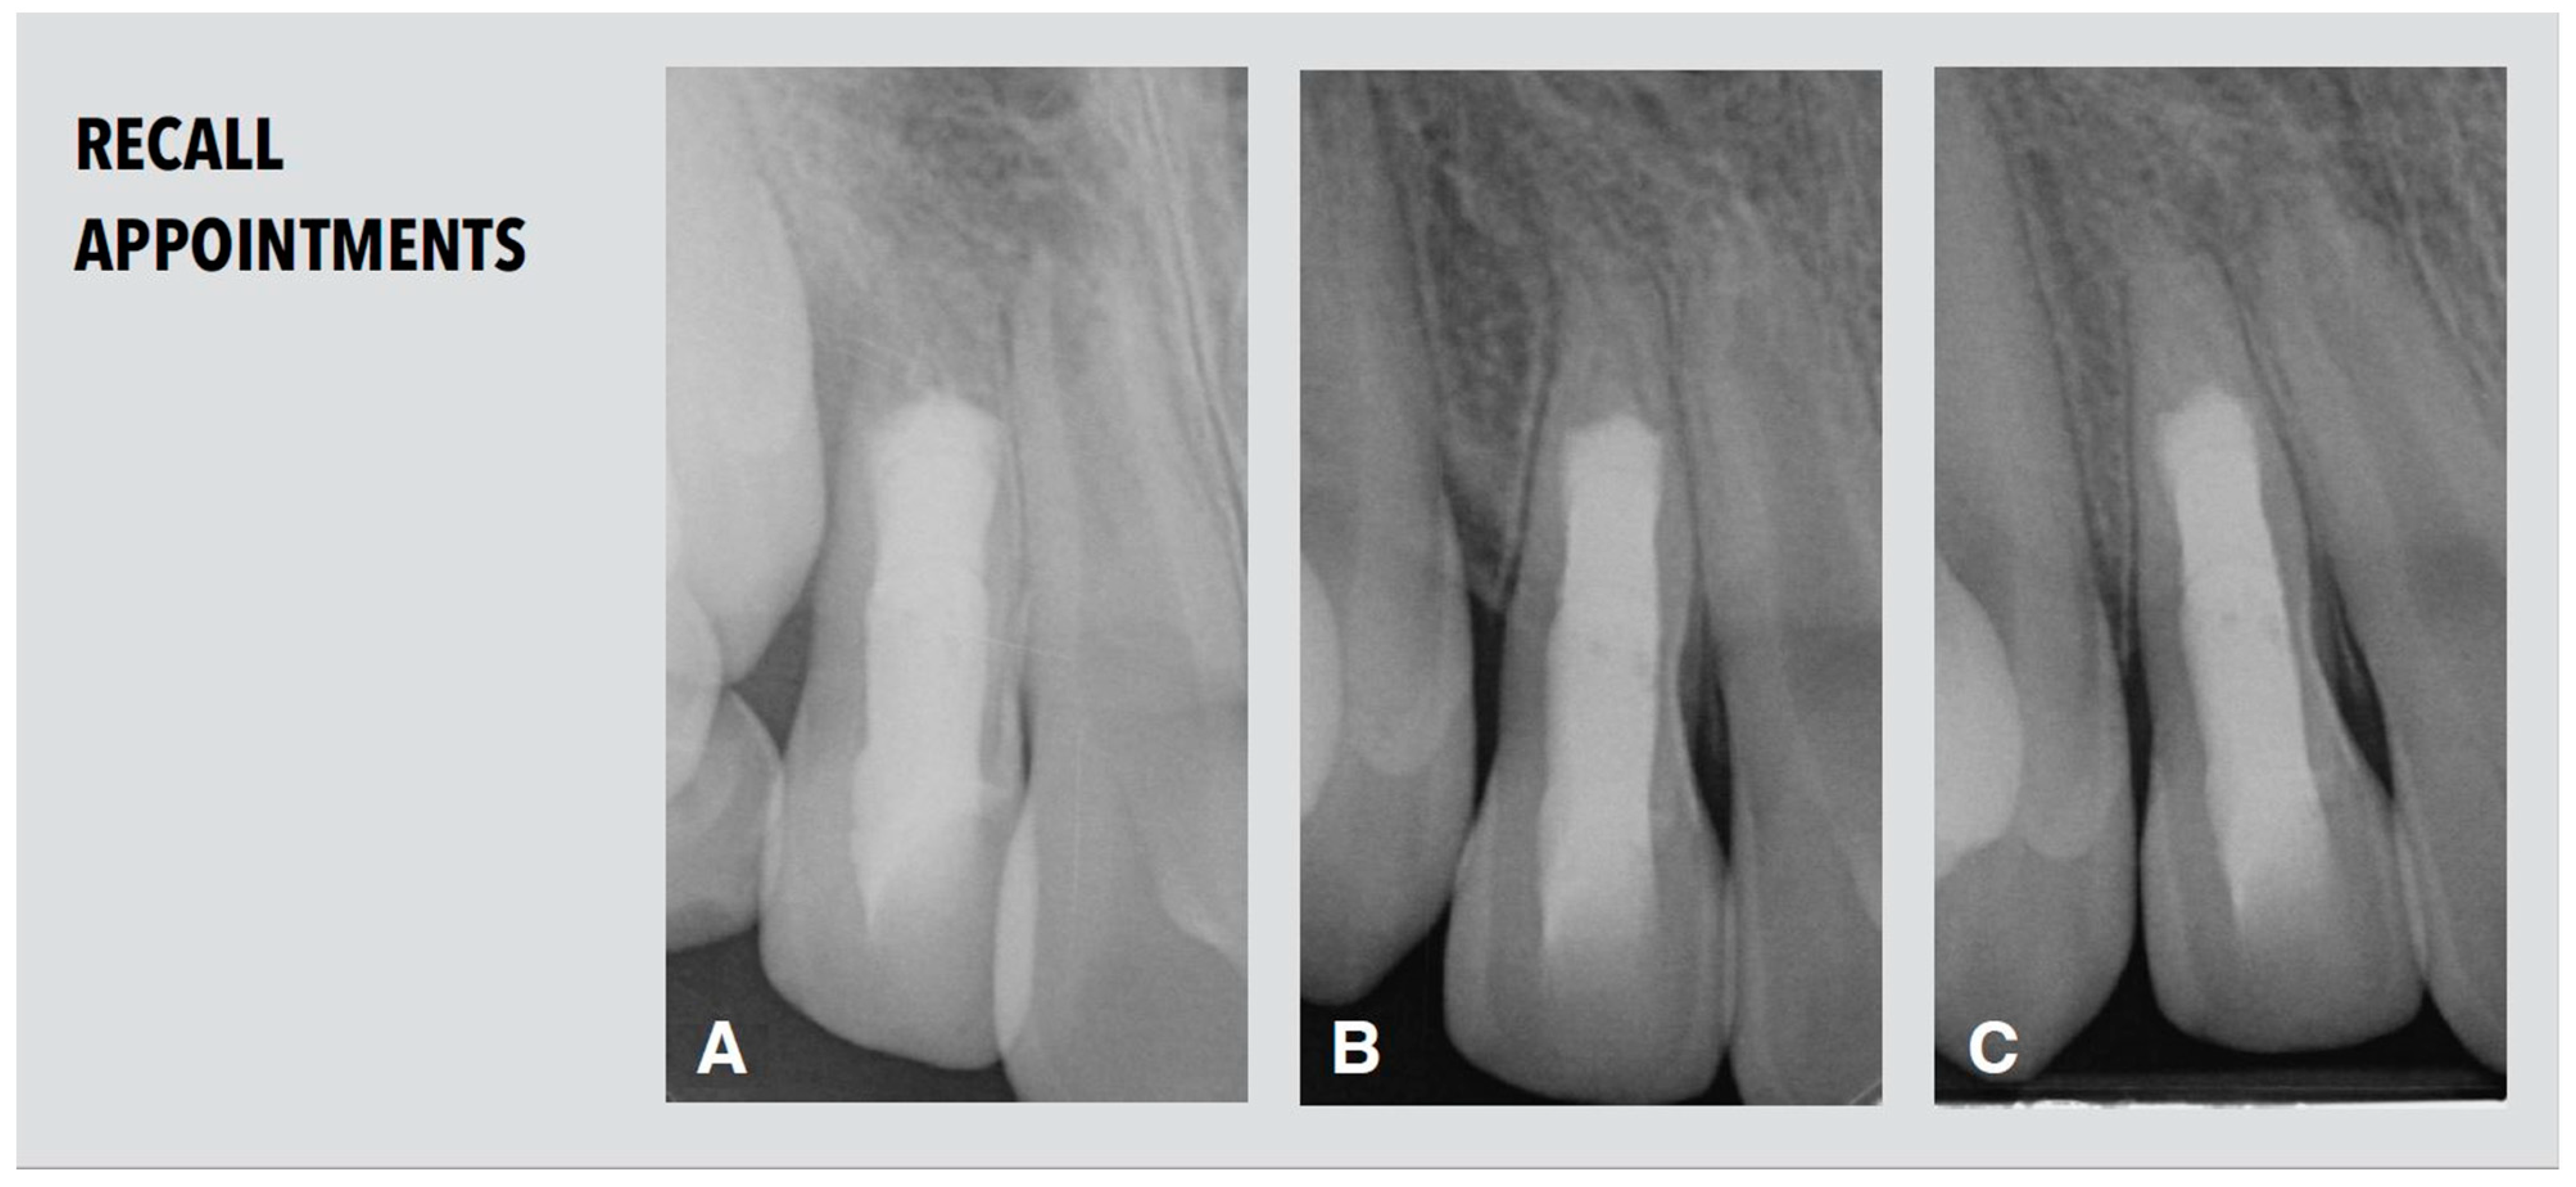

2.5. Recall Appointments

The patient attended the first recall appointment nine months after root canal filling. The tooth remained asymptomatic. Healing of the apical lesion and a considerable increase in both root length and thickness in the apical part below the MTA level was visible in the periapical radiograph (Figure 5A). Further root maturation was detected two years after treatment (Figure 5B).

Figure 5.

Radiological follow-up. (A) Periapical radiograph after nine months demonstrating increase in both root length and thickness in the apical part below the MTA level. (B,C) Periapical radiographs after two years (B) and after three years and nine month (C) demonstrating further root maturation.